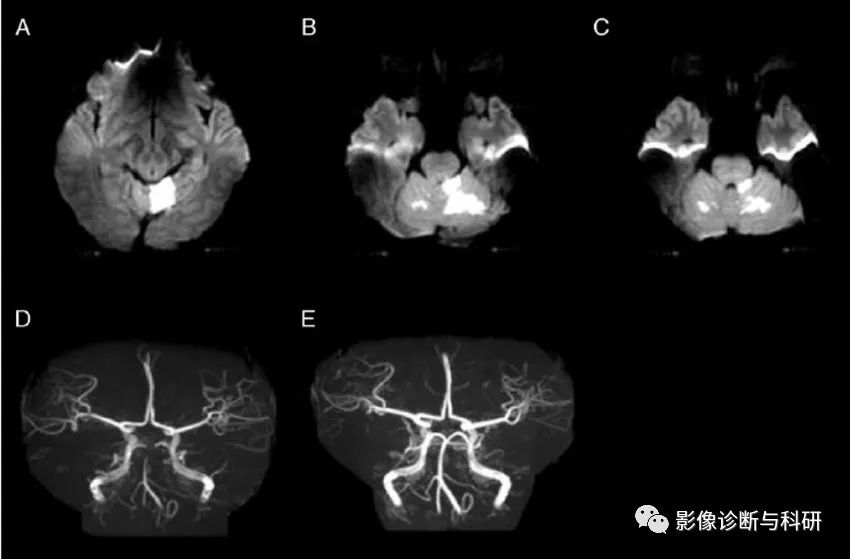

左侧小脑前下动脉 (AICA) 闭塞导致对应区域脑梗塞

弥散加权图像显示左侧脑桥臂和左侧小脑上外侧出现急性梗塞(a)。计算机断层扫描血管造影显示左侧椎动脉狭窄和闭塞,并且双侧小脑前下动脉(AICA)缺失(b)。DSA显示左近端 AICA 闭塞(c)

弥散加权图像显示左小脑前下动脉 (AICA) 区域梗死 ( a )。在磁共振血管造影中,左侧 AICA 缺失,而右侧 AICA 清晰可见 ( b )。基础平行解剖扫描磁共振成像(BPAS MRI)显示双侧 AICA 正常(c)

弥散加权图像显示右侧脑桥下外侧、脑桥臂和小脑上有高信号病变(a)。MRA( b),(c)显示右小脑前下动脉(AICA)未见显影